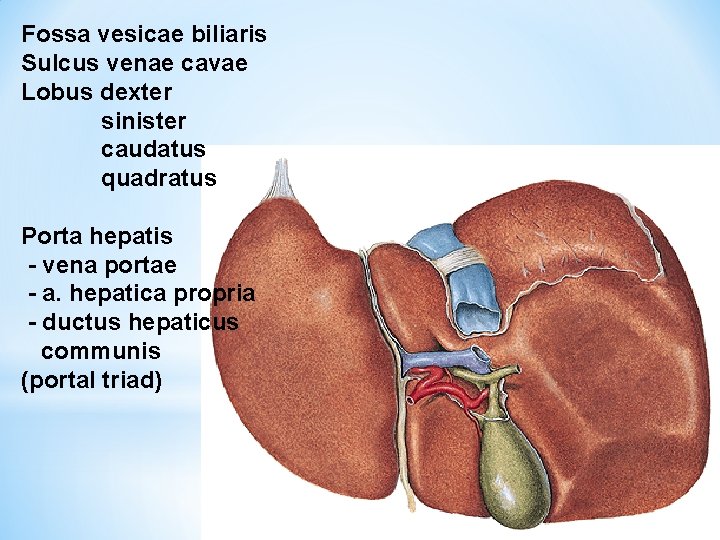

Fossa vesicae biliaris Sulcus venae cavae Lobus dexter sinister caudatus quadratus Porta hepatis - vena portae - a. hepatica propria - ductus hepaticus communis (portal triad)